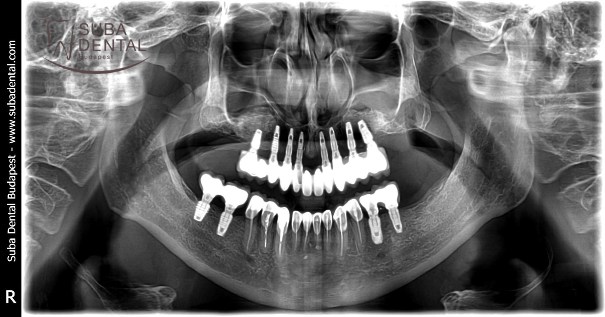

Panoramic radiograph following the mounting of 8 upper implants and the healing abutments